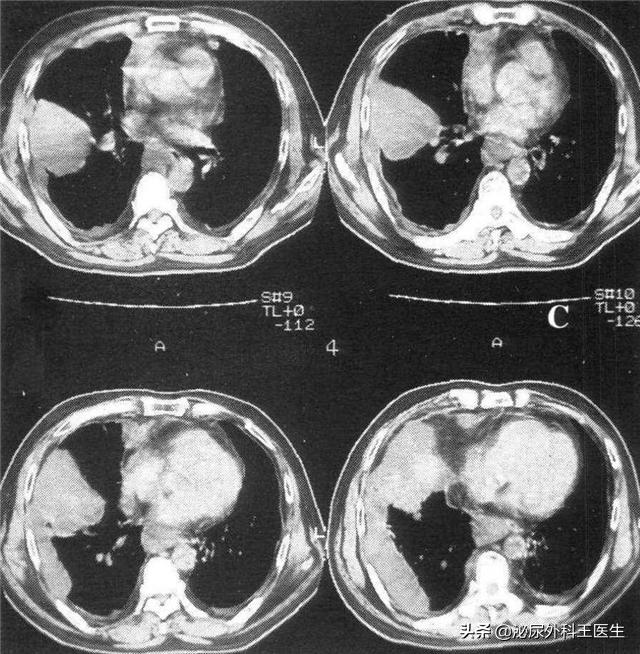

小王再一次来到我们医院,发现小王 右侧腹股沟有肿物 ,我们立即让小王入院治疗。检查发现 右侧腹股沟近耻骨联合处可见直径约1.5 cm肿大淋巴 。为确认小王淋巴实际大小,采用增强CT,见 淋巴结影 0.6 cm×1.3cm。 我们给出诊断: 阴茎侧腹股沟淋巴结转移。

活检结果显示,小王的术后病理为 淋巴结转移性鳞状细胞癌 。待小王伤口恢复后 行腹腔镜下腹部皮下双侧腹股沟淋巴结清扫术+经腹双侧盆腔淋巴结清扫术。 术后 无感染、无皮肤坏死、无双下肢水肿 ,术后恢复好。术后定期复查,发现左腹股沟浅淋巴结12枚、左腹股沟探淋巴结 1枚、右腹股沟浅淋巴结13枚、腹股沟深淋巴结3枚 均未见转移癌 。一切都在往好处发展。